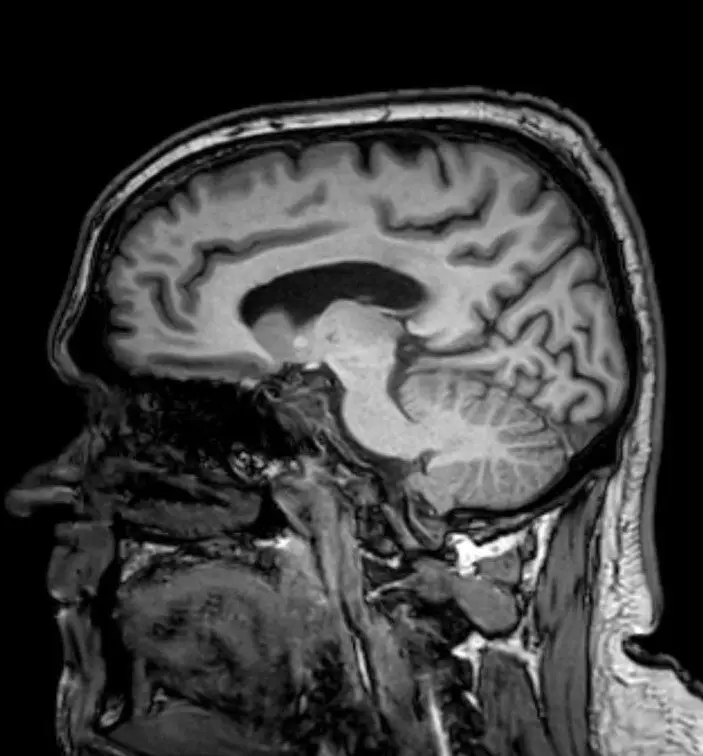

The business owner, from Derbyshire, had previously been told by GPs that his issues staying awake were down to low testosterone and a poor diet, but a CT scan after his crash revealed it to be something far worse.

Jamie had a glioblastoma, an aggressive and incurable form of brain cancer that saw him given just seven months to live.